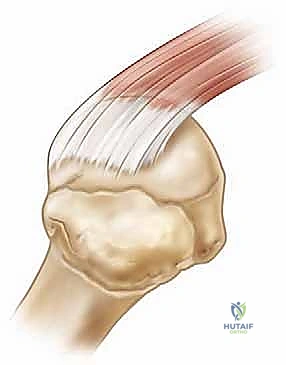

لفهم أهمية هذه الجراحة، يجب أولاً فهم التشريح المعقد لمفصل الكتف. يُعد مفصل الكتف (المفصل الحقاني العضدي) المفصل الأكثر مرونة وحرية في الحركة في جسم الإنسان بأكمله. ولكن، هذه الحرية الكبيرة تأتي على حساب الاستقرار. هنا يأتي دور "الكفة المدورة".

الكفة المدورة (Rotator Cuff) ليست عضلة واحدة، بل هي شبكة مكونة من أربع عضلات وأوتارها التي تغلف رأس عظمة العضد (Humeral Head) وتثبته داخل التجويف الكتفي الضحل. هذه العضلات الأربع هي:

1. العضلة فوق الشوكية (Supraspinatus): المسؤولة عن بدء رفع الذراع إلى الأعلى (وهي الأكثر عرضة للتمزق).

عندما تتمزق هذه الأوتار، تنفصل عن نقطة اتصالها بالعظم (البصمة العظمية)، مما يؤدي إلى فقدان التوتر الميكانيكي، وبالتالي الألم والضعف الشديد.